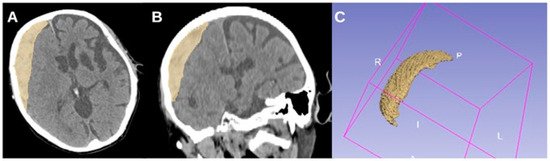

To illustrate this, Figure 3 and Figure 4 provide representative CT images of aSDH cases from our cohort with generalized seizures but different elongation values. Figure 3 shows a case with high elongation (1.99615), where the hematoma presents a markedly stretched, crescentic morphology with extensive cortical contact, aligning with our findings that higher elongation is associated with increased seizure risk. In contrast, Figure 4 depicts a case with lower elongation (1.38206).

Figure 4. CT axial (A), coronal (B), and 3D reconstruction (C) of an acute subdural hematoma with lower elongation (1.38206) in a 68-year-old female patient with generalized seizures.